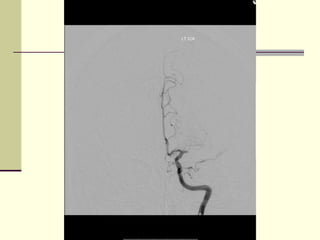

‫‪ MRA‬אנגיוגרפיה -‬

‫חוסר זרימה בעורק ה ‪MCA‬‬    ‫‪‬‬

‫מימין‬

‫רוב ההמיספרה הימנית לא‬   ‫‪‬‬

‫מקבלת דם‬